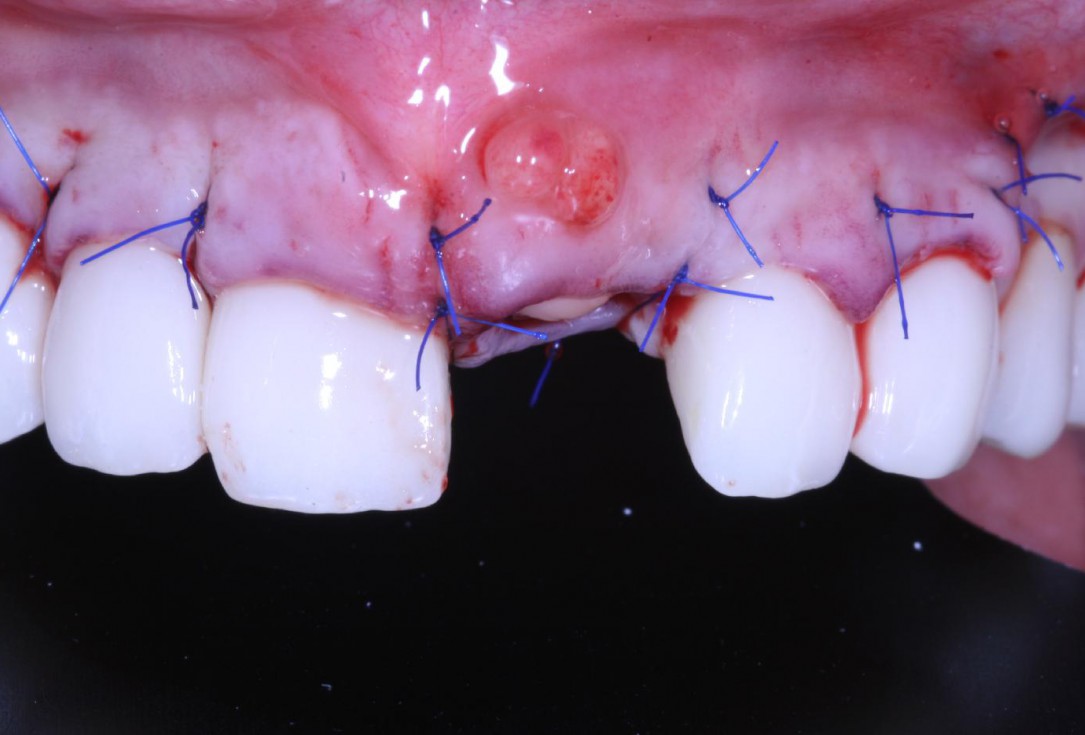

Socket seal with mucoderm® punch

Intact socket following atraumatic tooth extraction